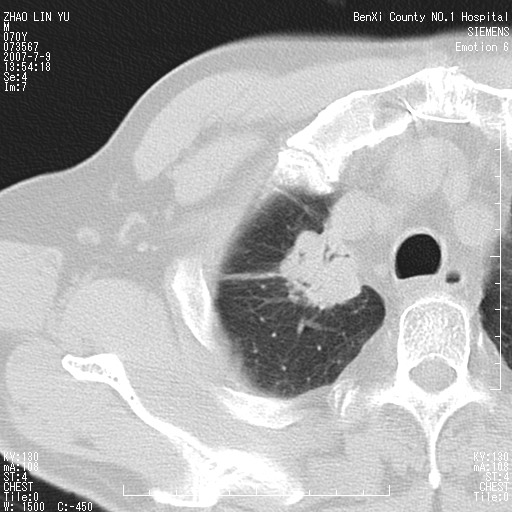

以下是引用王靖旗在2007-7-10 17:12:00的发言:[br] 男、70、咳嗽两个月,半年前换瓣手术,胸片未见异常,于昨天行x片发现右肺上野大片影,行ct扫描,这里是减薄图像,余肺正常。明天晚上会有增强扫描片,到时我会上传。[br][br] 冠状位请大家细看,应该是有意义的,[br][br] 请大家先看平扫发表意见。[br][br]

以下是引用zhangzhongshou在2007-7-10 21:43:00的发言:[br]右肺上叶周围型肺癌,以孤立型细支气管肺泡癌可能性大。